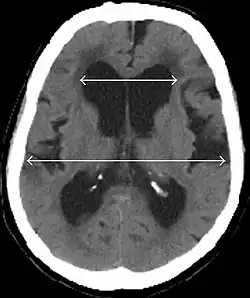

Evan's index is the ratio of maximum width of the frontal horns to the maximum width of the inner table of the cranium. An Evan's index more than 0.31 indicates hydrocephalus.[19]

• Imaging from magnetic resonance imaging (MRI) or computed tomography (CT) is needed to demonstrate enlarged ventricles and no macroscopic obstruction to cerebrospinal fluid flow. Imaging should show an enlargement to at least one of the temporal horns of lateral ventricles, and impingement against the falx cerebri resulting in a callosal angle ≤ 90° on the coronal view, showing evidence of altered brain water content, or normal active flow (which is referred to as "flow void") at the cerebral aqueduct and fourth ventricle.

MRI scans are the preferred imaging. The distinction between normal and enlarged ventricular size by cerebral atrophy is difficult to ascertain. Up to 80% of cases are unrecognized and untreated due to difficulty of diagnosis.[22] Imaging should also reveal the absence of any cerebral mass lesions or any signs of obstructions. Although all patients with NPH have enlarged ventricles, not all elderly patients with enlarged ventricles have primary NPH. Cerebral atrophy can cause enlarged ventricles, as well, and is referred to as hydrocephalus ex vacuo. For these reasons it's utmost important to note that Evan's index although commonly used in imaging is not very specific for NPH. One recent systematic review and meta-analysis suggests that callosal angle has high diagnostic performance and is commonly used together with Evan's index.[23]